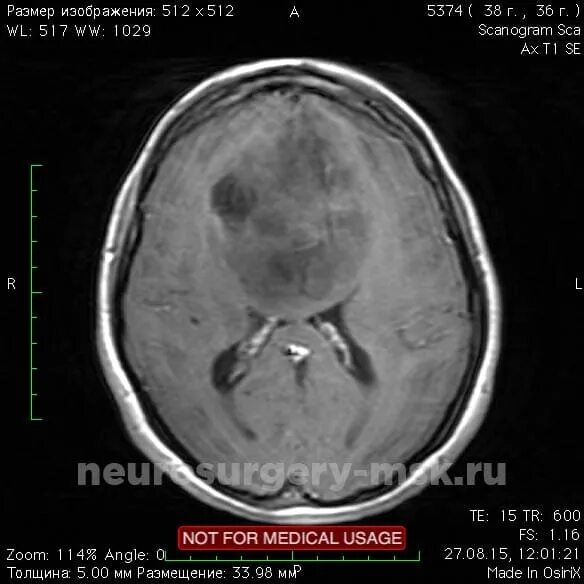

Астроцитома головного мозга прогноз после операции